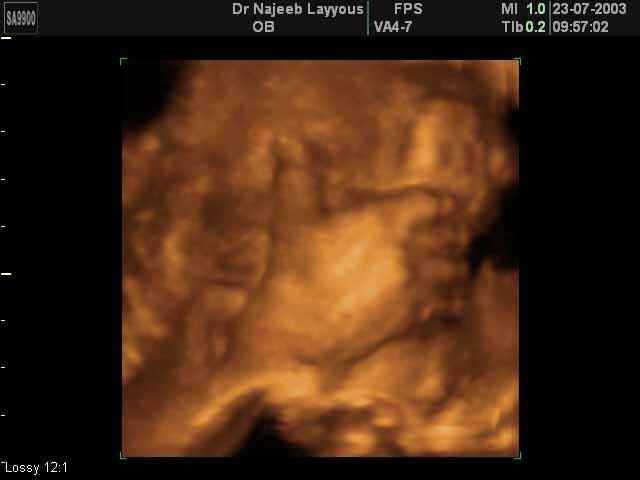

- 3D Fetal Limbs Ultrasound Scan Photos